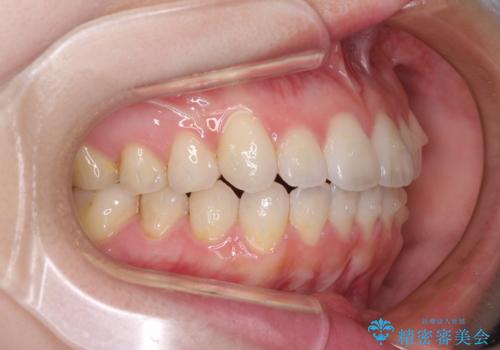

- 矯正治療の後戻りを気にして来院された患者様です。

後戻りは軽微でしたが、舌突出癖が認められ、初診時には上下前歯に舌がはまるスペースができていました。

舌突出癖の改善を行いながら、インビザライン・ライトにより矯正治療を行うこととしました。